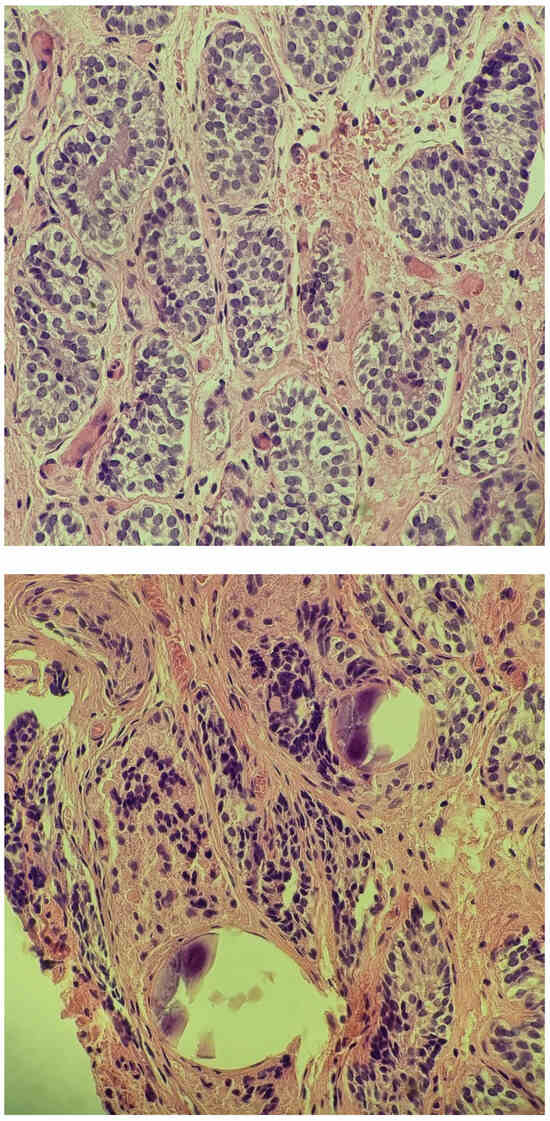

2.4. At Age 13 Years